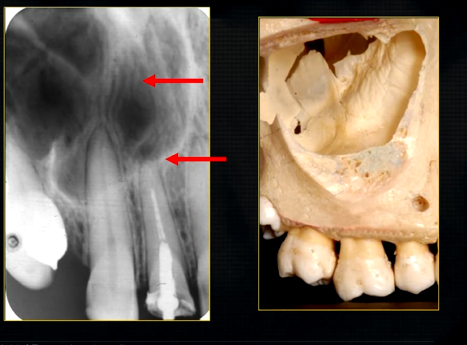

what does this anterior periapical graph show?

oval radiolucent area between the central incisors - is it Infront of the teeth (buccally?) or is it behind them? - you can’t tell radiographically

but its shape and position is compatible with the palatally positioned with the nasopalatine formaina

more posteriorly - radiopacities indicate the nasal septum and floor of the nose

dense, thin , white line in the middle of the image is the nasal septum

less dense opacity is caused by the

inferior nasal concha

radiolucency - nasal septum

lateral wall of the nose

maxillary air sinus

mid-palatal suture

this increased radiopacity is caused by the soft tissues at the tip of the nose - shadow - dense tissue